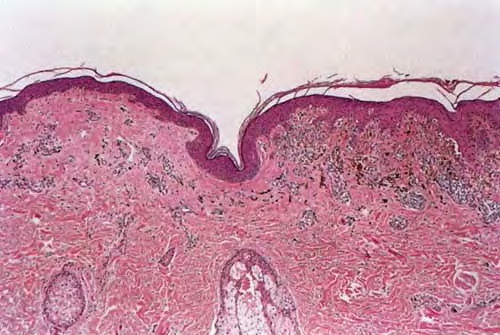

Regressing melanoma = الميلانوما المتراجعة